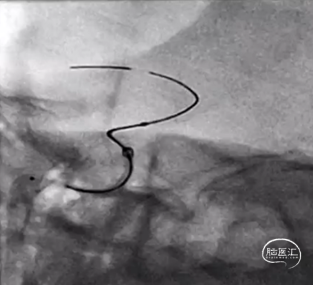

管生教授团队的姚智强教授同其组员一起为大家进行了Nuva®血流导向密网支架植入手术直播:

患者为女性,55岁,门诊以右侧眼动脉段动脉瘤,高血压收入科里进行治疗。入院行头颅MRI+MRA,可见右侧眼动脉段动脉瘤。术中造影,动脉瘤不规则且带有子囊,工作位测量动脉瘤大小约3.60×5.58mm,瘤颈约4.48mm,载瘤动脉远端3.88mm,近端约4.50mm。姚教授考虑到头端锚定位置要尽量避开脉络膜前动脉,术中释放过程中推拉结合所需操作的空间等,选择了TJED-D-5.0-18(预期血管直径4.5mm,预期长度25mm)的Nuva®血流导向密网支架。术中支架输送及打开顺畅,造影及术后支架重建可见支架贴壁良好。

在姚教授手术过程以及术后影像回顾中,会议现场管生教授、武汉协和医院的胡学斌教授、郑州大学第一附属医院徐浩文教授、哈尔滨医科大学附属第一医院吴培教授、西安交通大学第一附属医院于嘉教授、武汉脑科医院潘力教授、宜昌三峡中心人民医院汪雷教授、珠海市人民医院程光森教授对支架的头端锚定位置、支架选型、术中操作步骤等内容进行了热烈的讨论,并将会议气氛推向高潮。